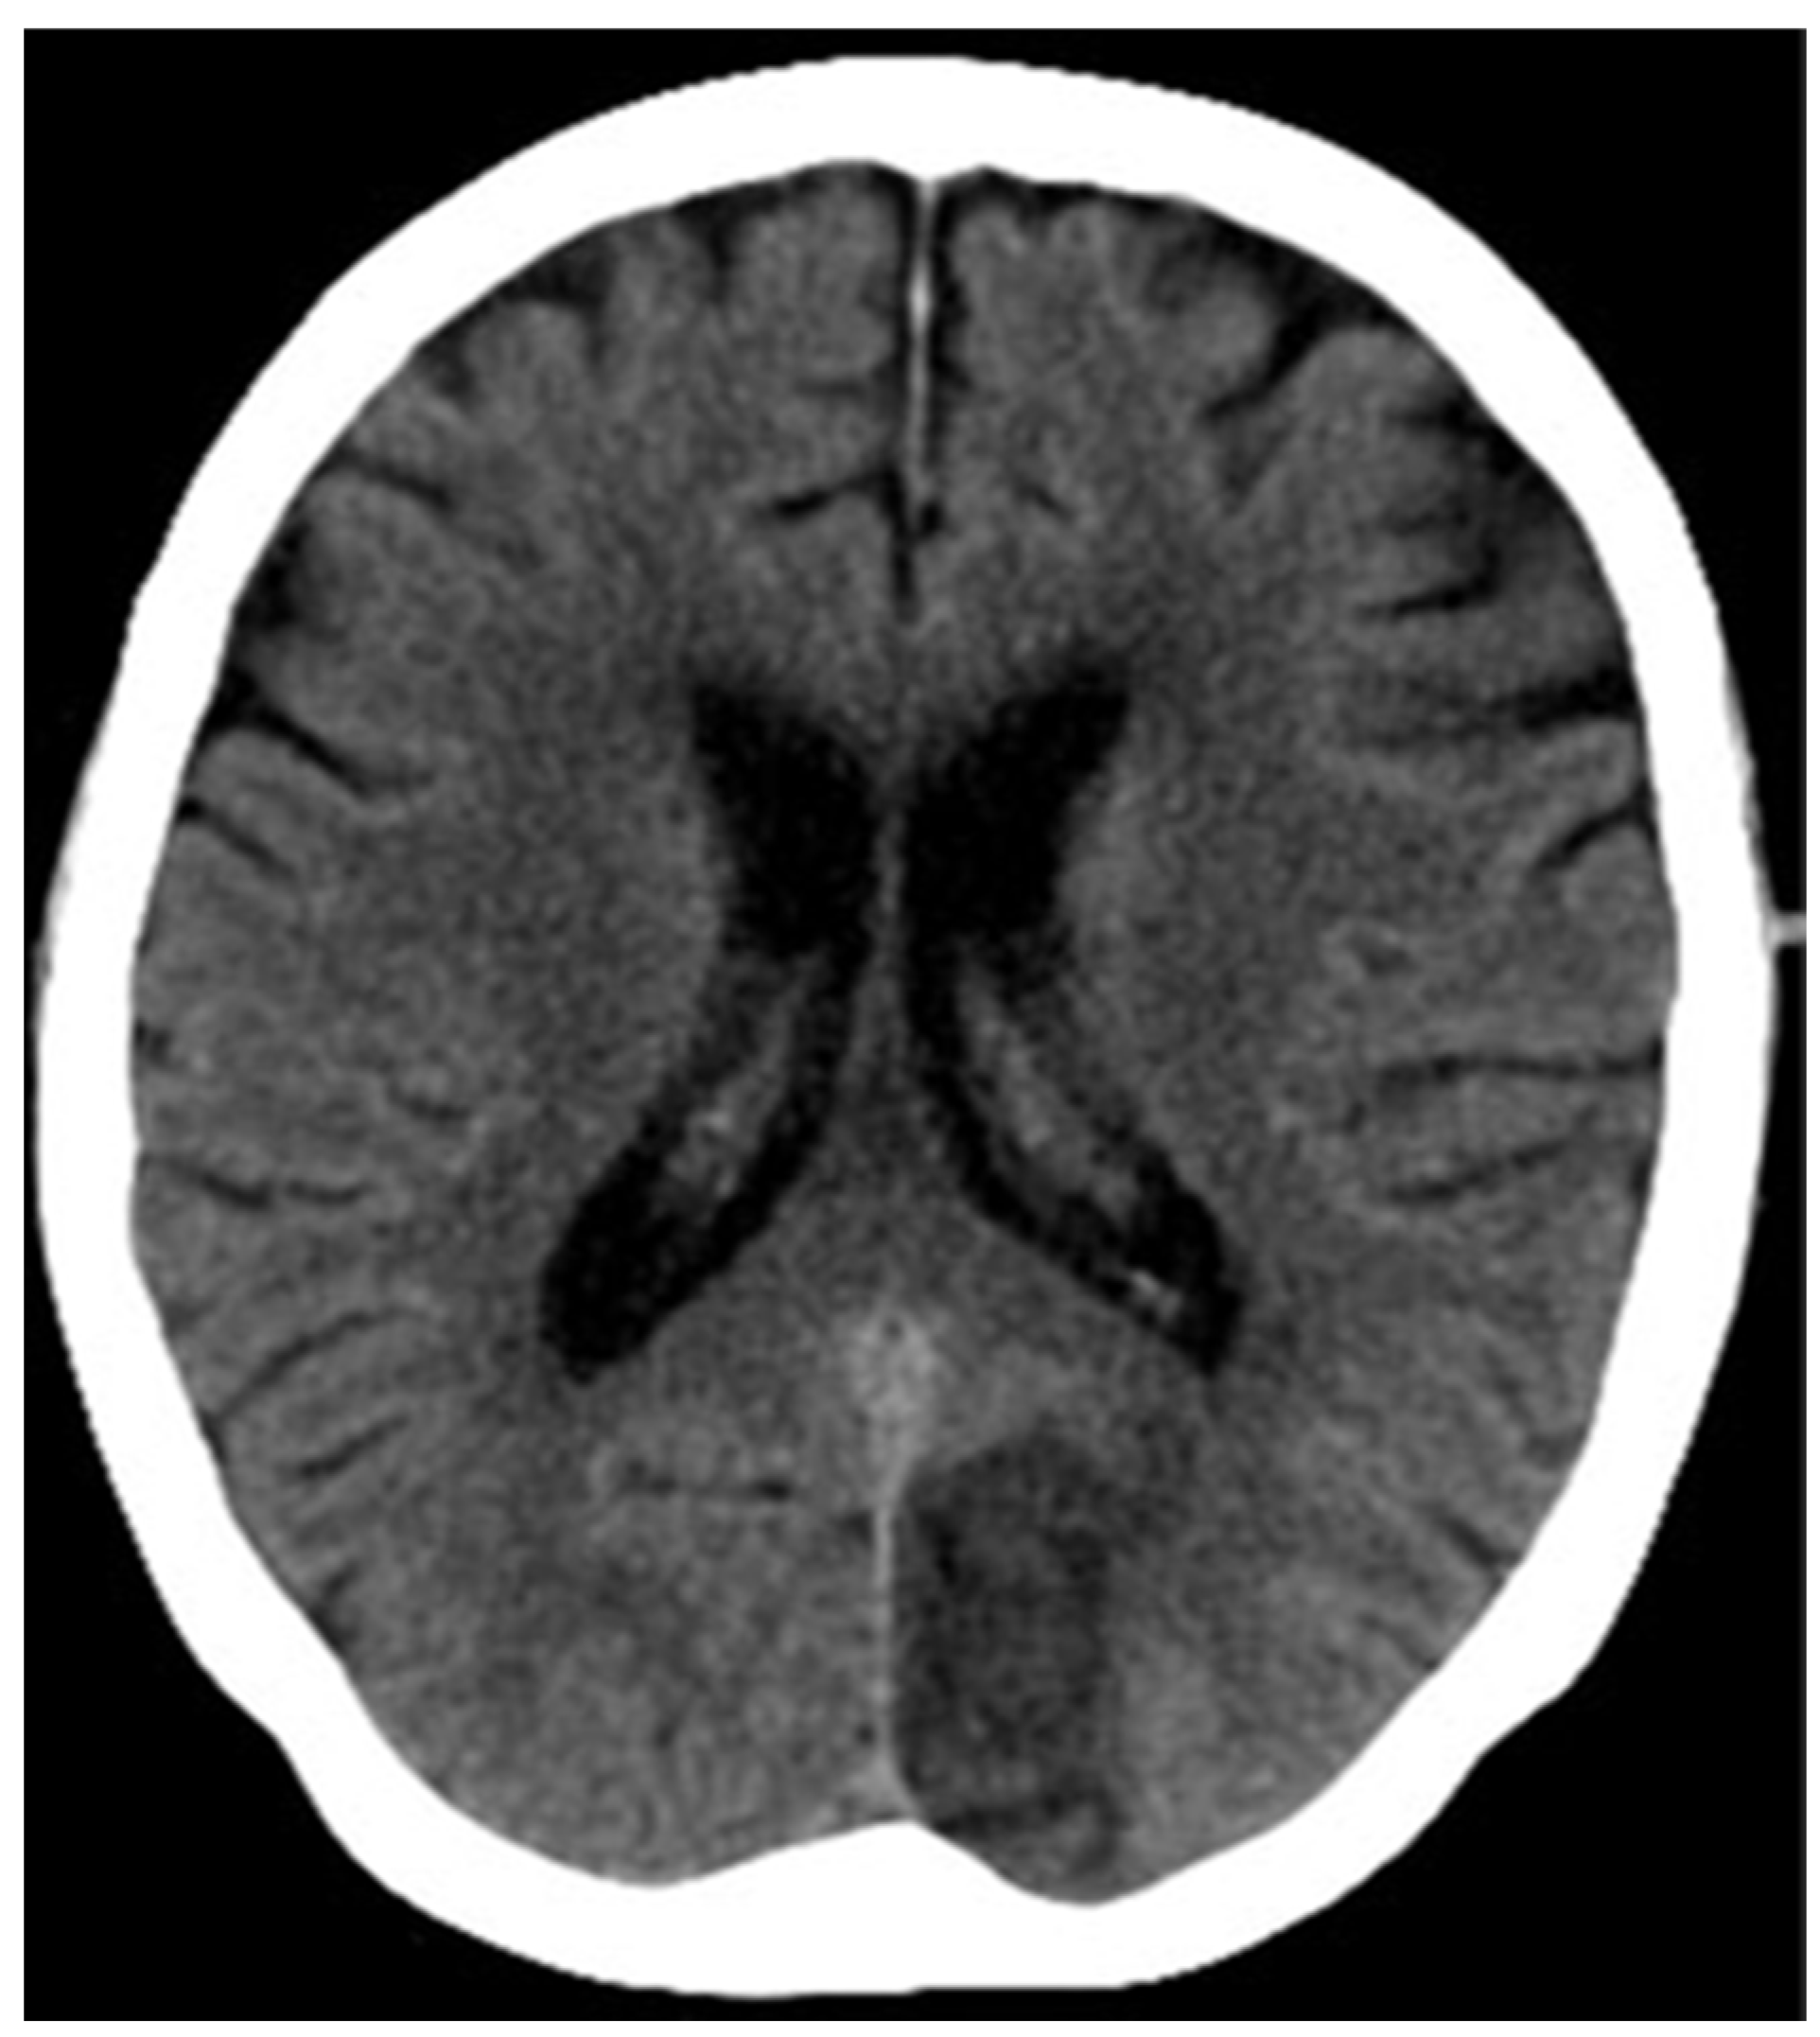

Case 2: A 67 -year-old man with cognitive dysfunction and minimal motor speech disorder since 1 day. CT shows an ill-defined hypodensity in the left caudate and left putamen region.

ASPECTS MCA- 8/10, ASPECTS PCA-10

The patient showed a good prognosis during follow-up after 15 days.

Figure 2. NCCT of case 2.